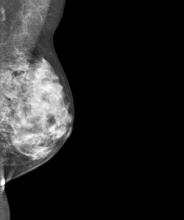

Sutter Pacific Medical Foundation Women’s Health Center is in Santa Rosa, Calif., a community of 160,000 located an hour north of San Francisco in an area that is perhaps most prominently known as the Sonoma wine country.  Our breast center, which screens 10,000 women per year, has established a regional reputation as a center of excellence in the detection and diagnosis of breast disease.